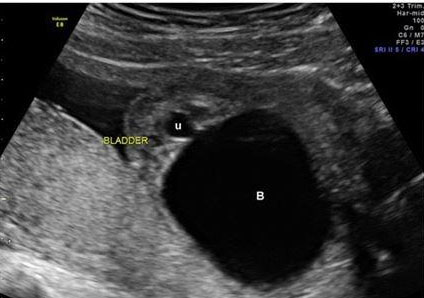

The best diagnostic clue is a dilated upper collecting system and a ureterocele within the urinary bladder (Figure 7). Kidneys should be evaluated in transverse and longitudinal planes (Figure 8).

The ureterocele is seen as a cystic structure within the fetal urinary bladder. The ureterocele is associated with the ectopic insertion of the ureter draining the upper pelvis.

Weigert–Meyer rule: Ectopic upper pole ureter insertion inferior and medial to normotopic ureter in trigone of the bladder, usually associated with ureterocele in bladder. Upper pelvis dilated from obstruction, lower pelvis refluxes (Figure 7 and Figure 8).

Figure 7: Ultrasound image showing a ureterocele (part of the ureter that inserts into the bladder forming a cystic structure) in the urinary bladder [19]. Radiological images were obtained from open-access article distributed under the terms of the Creative Commons Attribution License (CC BY) [19].